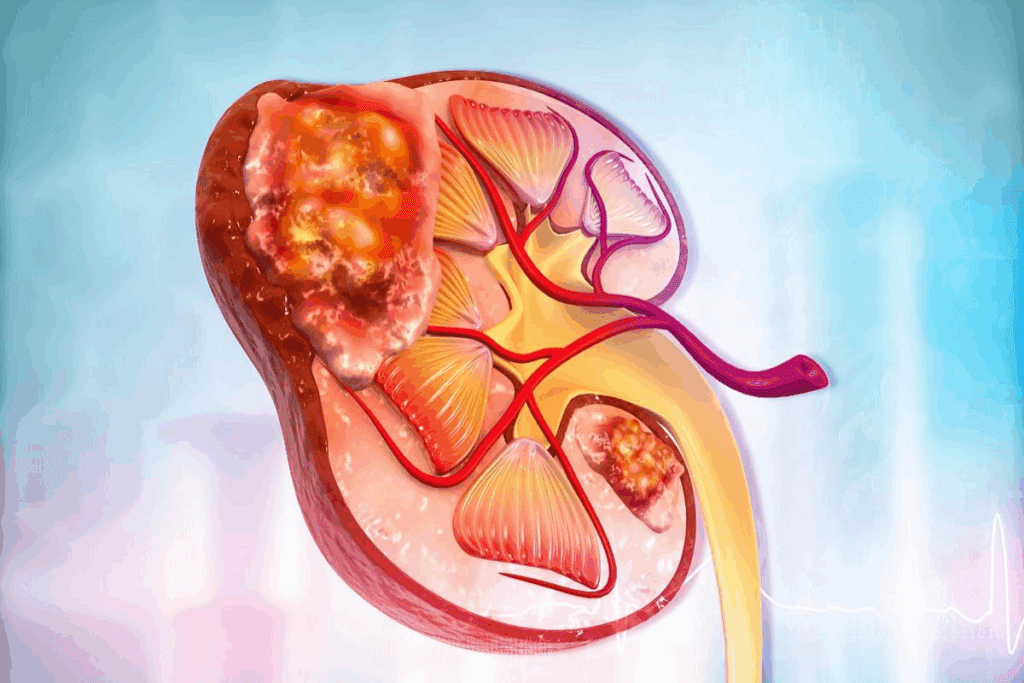

It’s important to know about kidney tumors to plan the best treatment. Most kidney cancers are renal cell carcinoma. These tumors can be harmless or cancerous.

Types and Stages of Kidney Tumors

Kidney tumors are divided by their type and how they grow. Renal cell carcinoma starts in the kidney’s lining. It’s the most common kidney cancer in adults.

The cancer’s stage is key for treatment. For small tumors, surgery is often the best choice. This helps keep the kidney working well.